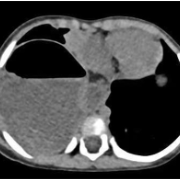

这一个多月来,1岁2个月的依依每次吃奶后都会呕吐、腹泻,反反复复不见好。焦急的家人带她到当地医院就诊,为了查清病因,医生为她安排了腹部CT检查。结果却出乎所有人的意料——依依的胃,竟然不在它应该在的腹腔里,而是穿过分隔胸腔和腹腔的肌肉层,“跑”进了右侧胸腔。

这个意外发现让家人意识到问题的严重性。为了明确诊断,他们带着依依来到湘雅医院。进一步的检查确认,依依患的是一种先天性结构畸形,叫做“食管裂孔疝”,同时还伴有胃-食管反流。正常情况下,食管穿过膈肌进入腹腔的那个通道,在依依身上变得异常宽大,以至于胃,甚至部分结肠都从这个缺口挤进了胸腔。这不仅导致她吃进去的食物无法正常消化吸收,引起呕吐和营养不良,更严重的是,移位的内脏还压迫了她的右肺,导致肺叶无法充分张开,甚至引发了肺部感染。